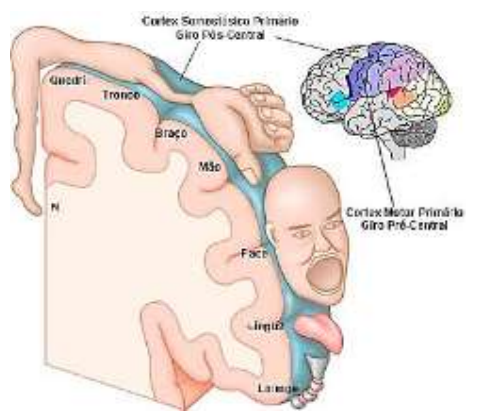

A figuras abaixo retrata a imagem do “Homúnculo de Peinfield” que representa a somatotopia (correspondência ponto a ponto de uma área do corpo com um ponto específico do sistema nervoso central) das áreas corticais primárias sensitiva e motora. O conhecimento do suprimento arterial destas estruturas é imperativa para o correto entendimento dos Acidentes Vasculares Encefálicos (AVEs) e sua clínica característica.

Com base nos seus conhecimentos sobre neuroanatomia e sobre o suprimento da porção medial do homunculo de peinfield (Correspondente à área somatotópica de quadril, perna e pé) no cortex sensitivo/motor, assinale a alternativa correta.